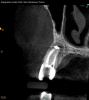

Lastly, regardless of the treatment approach pursued, it is essential to tend to the psychological needs of the patient experiencing a flare-up. The patient should be reassured that the condition is treatable and that flare-ups are quite distinct from treatment failure. In fact, their occurrence has not been shown to affect the overall prognosis of NSRCT (Figure 2 through Figure 5).39,40 Because significant preoperative pain complaints have been associated with a greater risk of flare-up, these patients should be counseled and duly warned of the possible occurrence of a flare-up. Simple discussions on pain management and after-hours emergency availability can significantly reduce the stress of flare-ups for providers and patients alike.14

Fig 4. Case demonstrating successful healing of tooth No. 5 following a flare-up incident. Fig 2: Patient presented with asymptomatic apical periodontitis of tooth No. 5. Fig 3: Following initiation of NSRCT, the patient developed a flare-up with swelling and pain. Amoxicillin was prescribed and the calcium hydroxide medicament was replaced. Fig 4: The patient returned 3 months later with radiographic healing of the apical periodontium. Fig 5: Obturation was completed.

Figure 4